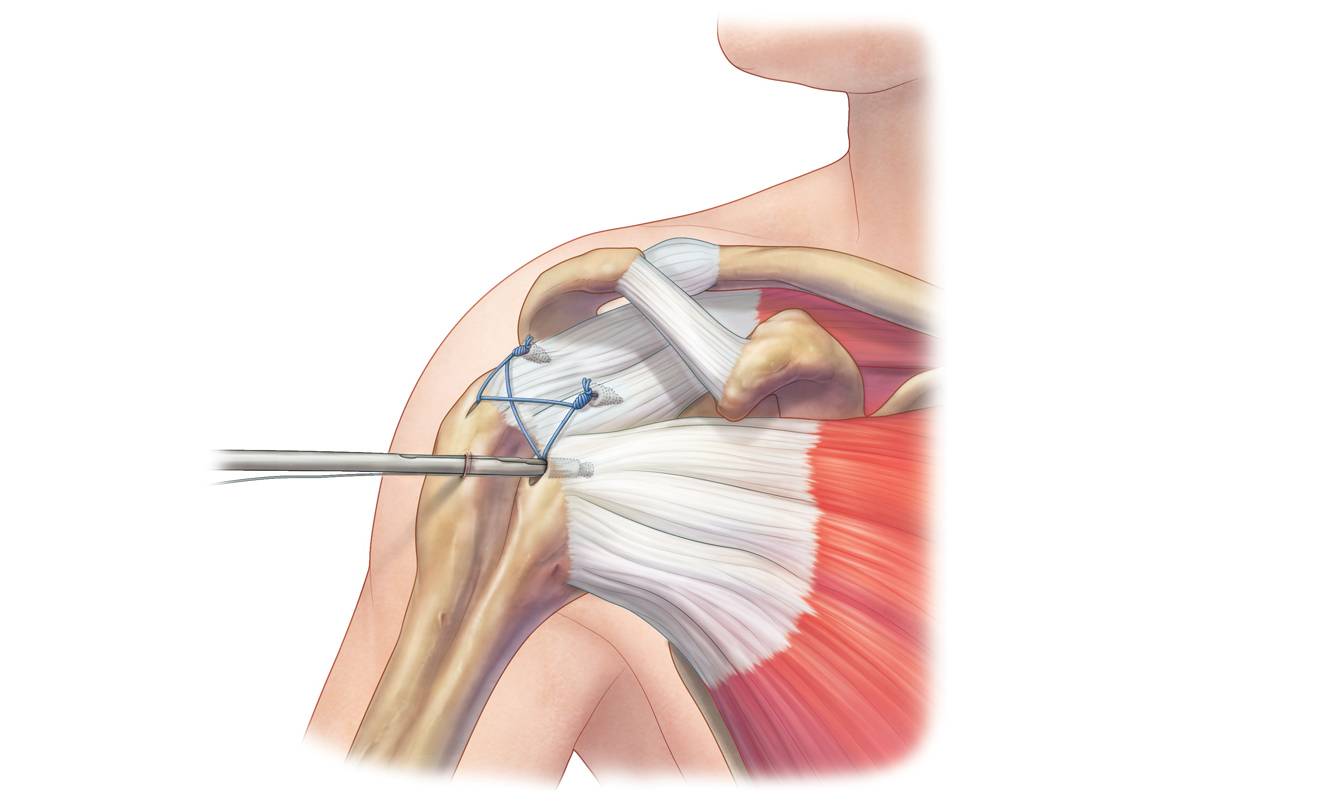

Фотографии мышц ротаторной манжеты плеча